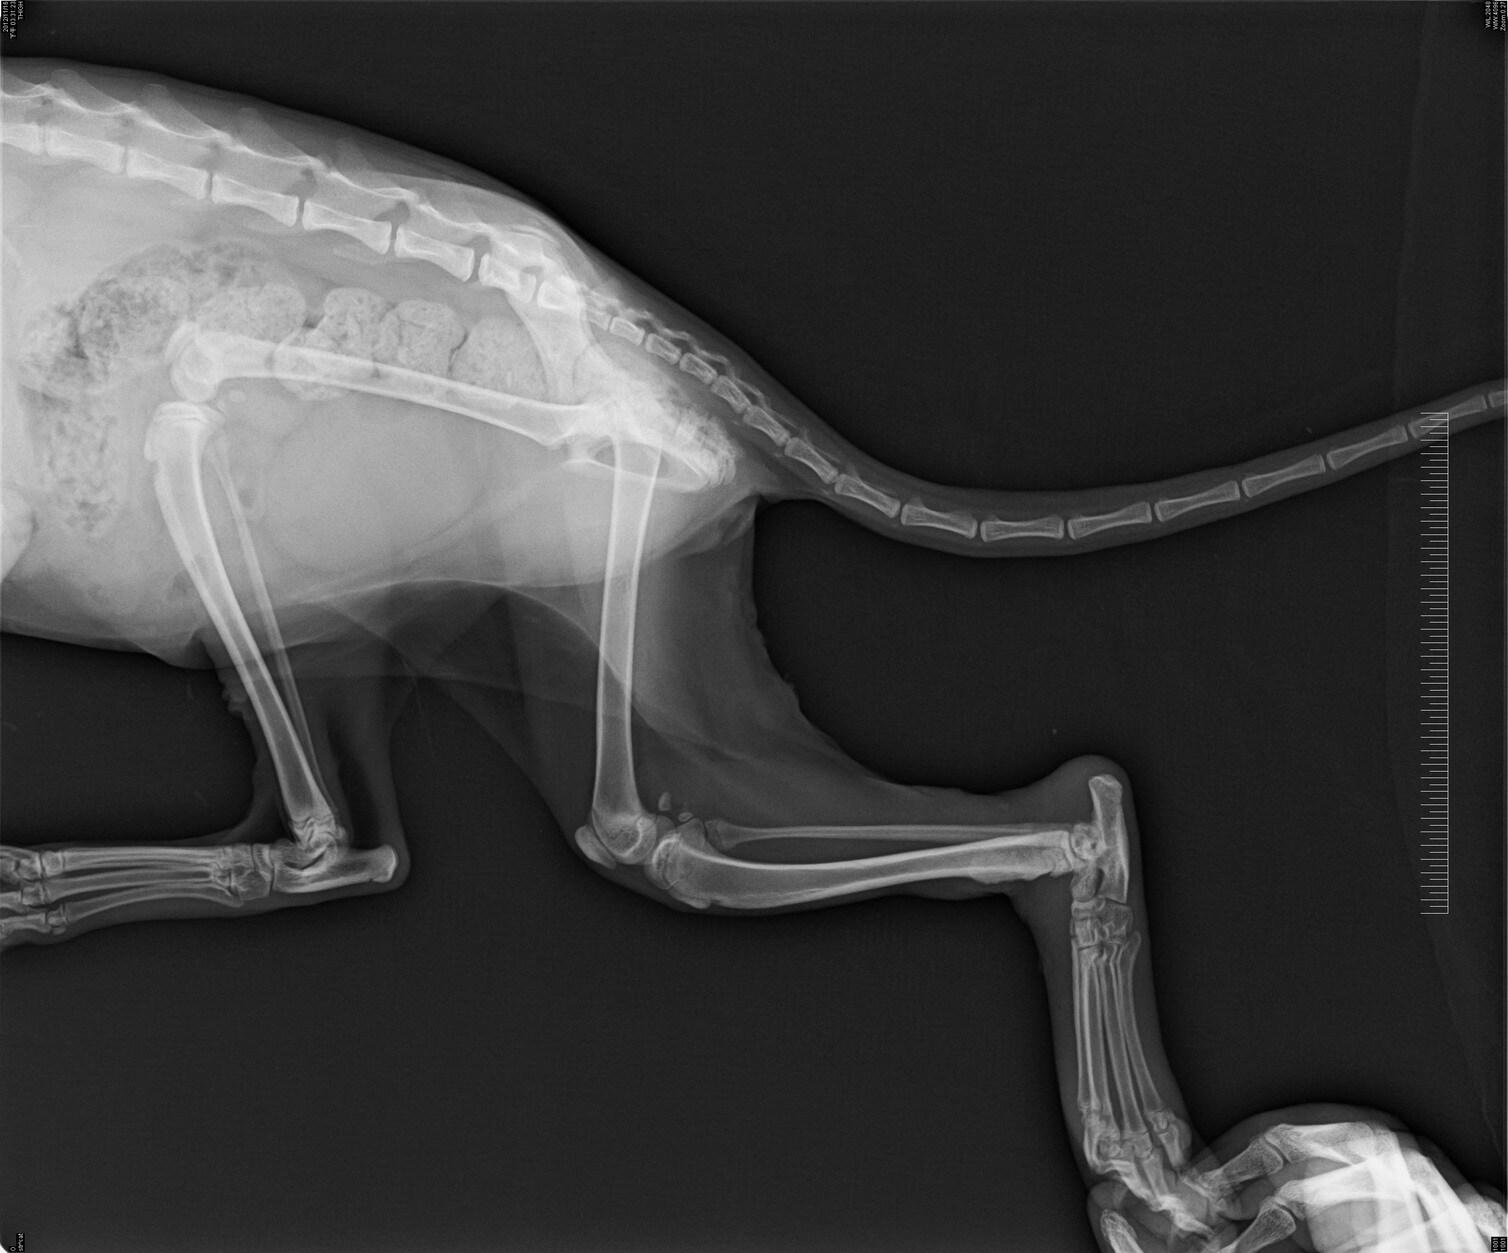

- 編號: 1437

主題: 烏來桂山路腿傷喵求援 申請者姓名: Jill Ringo 花色: 申請日期: 2012-11-21 14:23:12 申請者部落格: http://jilltgh002.pixnet.net/album 申請者臉書網址: https://www.facebook.com/jill.ringo?ref=tn_tnmn 所在縣市/合作醫院: 新北市/喬伊動物醫院 治療費用: 1650元 需求人數: 4人 已結案 (2013-06-27 14:05:11) 報名人員: 香香君(已付款)、香香君(已付款)、伶伶(已付款)、伶伶(已付款)、 候補人員: 動物病情說明: 這隻喵喵是愛媽求援的,我幫忙申請醫助。

愛媽一向是餵養美之城的浪喵喵,

近期餵到烏來桂山去,

發現一隻橘喵腳腳疑似被彈簧床的彈簧勾纏住,

已掙脫但腳腫大有外傷,用三隻腳走路,

愛媽借了誘捕籠自行將喵喵誘捕到後送醫,

幸好救援及時傷沒深及骨頭,

醫生判斷需住院一周讓外傷痊癒。

愛媽擔心住院費用高,已找到朋友願中途喵喵養傷,

後續考慮幫喵喵找家。

2天住院醫療費用需要大家幫忙~非常感謝~